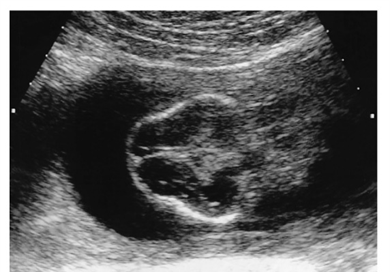

What is this image showing?

Coronal view of facial structures (maxilla, upper lip, mandible, nasal bones, lower eyelids

Transverse View

Transverse view of fetal face